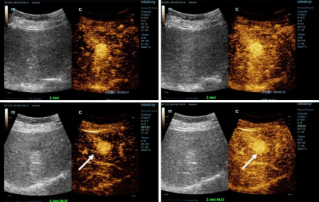

![more-precise-diagnoses-with-hifr-ceus.thumb.319.319 DiagnĂłsticos mĂĄs precisos con HiFR CEUS]() DiagnĂłsticos mĂĄs precisos con HiFR CEUSLa ecografĂa potenciada con contraste (CEUS) es un campo muy dinĂĄmico y en los Ășltimos a?os las innovaciones tecnolĂłgicas han aumentado aĂșn mĂĄs la calidad de la imagen. Una de estas innovaciones es la ecografĂa potenciada con contraste de alto frame-rate(HiFR CEUS), que puede generar hasta diez veces mĂĄs imĂĄgenes que el ultrasonido convencional, sin demorar mĂĄs tiempo.EcografĂa | ImĂĄgenes medicina general 2023-04-28

DiagnĂłsticos mĂĄs precisos con HiFR CEUSLa ecografĂa potenciada con contraste (CEUS) es un campo muy dinĂĄmico y en los Ășltimos a?os las innovaciones tecnolĂłgicas han aumentado aĂșn mĂĄs la calidad de la imagen. Una de estas innovaciones es la ecografĂa potenciada con contraste de alto frame-rate(HiFR CEUS), que puede generar hasta diez veces mĂĄs imĂĄgenes que el ultrasonido convencional, sin demorar mĂĄs tiempo.EcografĂa | ImĂĄgenes medicina general 2023-04-28 -